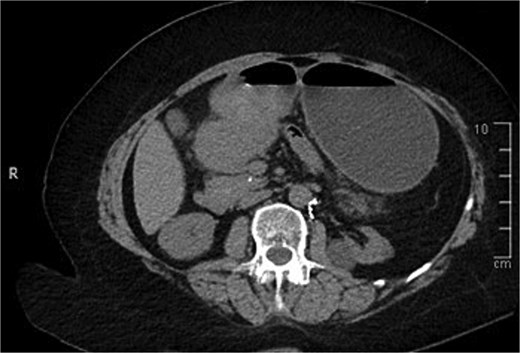

A computed tomography (CT) of the abdomen with IV portal venous contrast demonstrated proximal gastric dilatation due to a 7.6 cm gastric pyloric mass concerning for malignancy (Fig. 1). Other findings included small volume pancreatic parenchymal calcifications with no ductal dilatation. She was decompressed via nasogastric tube and planned for gastroscopy and feeding tube insertion. Gastroscopy demonstrated a partially obstructing extraluminal mass at the gastric antrum, able to be traversed to the second part of the duodenum (Fig. 2). A nasojejunal feeding tube was placed and the nasogastric tube was left in for decompression. An endoscopic ultrasound the following day demonstrated Doppler signal in the mass, confirmed to be a large 6.2 × 4.2 × 7.0 cm pseudoaneurysm arising from the GDA on a subsequent CT mesenteric angiogram (Fig. 3). Coil angioembolization of the pseudoaneurysm was successfully done via common femoral access (Fig. 4). She was commenced on NJ feeding and supplemental parenteral nutrition. She recovered well and was discharged on puree diet. Repeat imaging at 4 weeks demonstrated resolution of the pseudoaneurysm and returned to normal diet 6 weeks post presentation.

Endoscopic photograph showing large partially obstructing extraluminal mass at the gastric antrum.